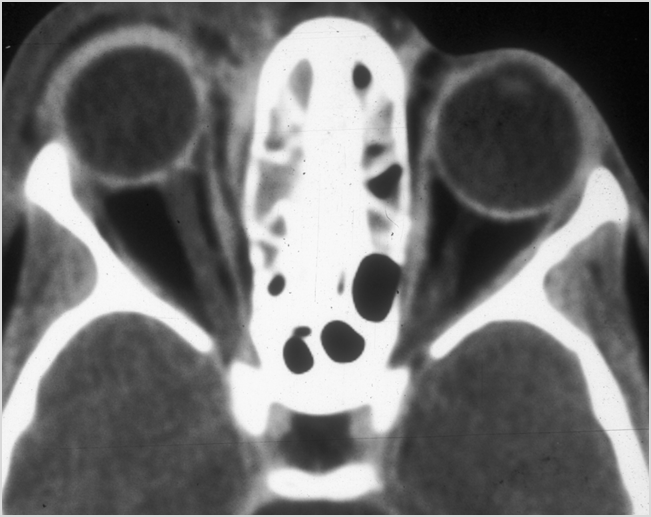

Orbits

The extraconal orbital fat is abnormal. [Yes/No]

There is a subperiosteal abscess or edema along the medial wall, roof or floor of the orbit. [Yes/No]

The extraocular muscles are swollen or otherwise abnormal. [Yes/No]

There is bone erosion along the walls of the orbit. [Yes/No]

The intraconal orbital fat is infiltrated. [Yes/No]

The orbital apex and the superior and inferior orbital fissures are infiltrated. [Yes/No]

The superior and/or inferior ophthalmic veins are dilated or thrombosed. [Yes/No]

Eyes

Proptosis is present. [Yes/No]

The optic nerve is stretched in appearance. [Yes/No]

The posterior aspect of the globe is tented in appearance. [Yes/No]

The uveal scleral margin of the globe is swollen or enhancing abnormally. [Yes/No]

Signs of tension orbit or endophthalmitis are present. [Yes/No]